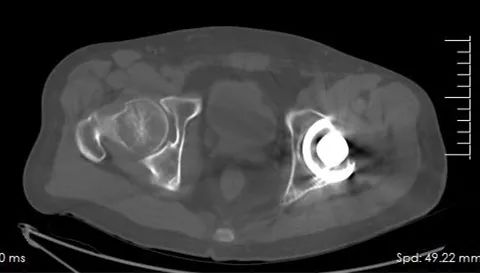

张先生因左股骨颈骨折于骨一科成功进行了左股骨头置换手术,可当需要进行影像学检查复查时,大夫们犯了难,由于置换物属于金属物质,扫描时很容易对周围组织产生伪影,不利于诊断。

这台能谱CT可以解决这个问题吗?

张先生和医生心里打了一个大大的问号

让我们一起试试看吧!

“选择能谱扫描序列”→“选择扫描范围”→“扫描启动”→“扫描完毕”→“图像后处理”

仅用了数十秒的时间,检查已经完成。当处理后的图像展示在大家眼前时,张先生和医生的疑虑被彻底打消了,处理后的图像去除了大部分的伪影,使周围的组织情况变得更加清晰,便于医生们做出更明确的诊断。通过此次检查,张先生得知自己恢复良好,悬着的心终于放下了。